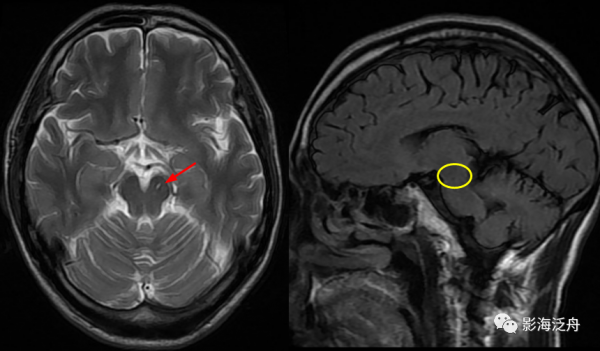

![]()

III型-中腦型:左側大腦腳可見細條狀T2WI高訊號影(紅箭),Flair序列上未見異常訊號(黃圈為中腦左側部),隨訪病灶大小及訊號均無明顯變化。III型VR腔隙擴大是最少見的,多數稽核老師喜歡不分青紅皂白直接診斷為腔梗灶,畢竟是腦幹區域,報的過一點也無妨。